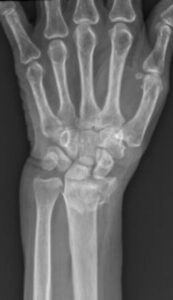

The distal radius is the end of the forearm bone closest to the wrist. A break in this area is called a distal radius fracture. It can range from a simple crack to a complex fracture involving joint surfaces.

Dr. Ehab Aldlyami conducts a thorough clinical assessment and uses imaging tools such as X-rays and CT scans to determine:

- The type of fracture (displaced, comminuted, intra-articular, etc.)